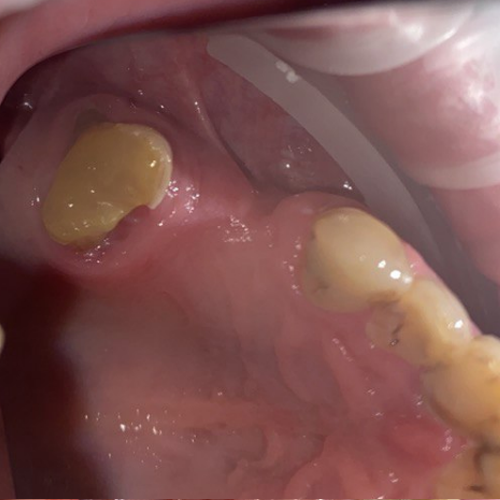

It'sGeorgy Опубликовано 29 мая, 2021 Автор Поделиться Опубликовано 29 мая, 2021 (изменено) Всем спасибо за отклик. Через 2 мес, если не забуду, выложу фото результата. 28.05.2021 в 22:17, АнтонТЛТ сказал: Какой смысл в свободном трансплантате был? По плану было увеличить объем вестибулярно и толщину окклюзионно, чтобы в дальнейшем, на этапе времяшек, дополнительно сместить все в сторону этого дефекта, чтобы его закрыть: 11 часов назад, Женька сказал: Не слишком ли высоко трансплантат забран? не критикую, только интересуюсь. Сложно сказать. При заборе трансп с неба я иглой во время анестезии смотрю участок, где достаточная толщина. Вероятно, в момент операции, эта область показалась наиболее перспективной с этой точки зрения. Сейчас, как сказал @Карен Аванесов , я бы вообще с бугра взял. Да и в целом, с десной бы работал на этапе высоких формиков. Изменено 29 мая, 2021 пользователем It'sGeorgy Ссылка на комментарий

It'sGeorgy Опубликовано 12 июня, 2021 Автор Поделиться Опубликовано 12 июня, 2021 Прошу прощения, что долго не получилось ответить. 03.06.2021 в 00:11, АнтонТЛТ сказал: Я правильно понимаю, что установлены короткие фдм, подшит трансплантат, не было мобилизации и рана ушита наглухо? Верно. 03.06.2021 в 00:11, АнтонТЛТ сказал: Если да, то за счёт чего получилось ушить наглухо? Выходит, что за счет излишнего натяжения. Но, во время операции, мне не показалось, что я сильно что-то тягу. 03.06.2021 в 00:11, АнтонТЛТ сказал: Трансплантат получается не вестибулярно, а окклюзионно пришит. Да. В целом, хотел, чтобы было так: Трансп лежит частично над имплантатами, частично - вестибулярно под лоскутом. Лоскут фиксируется небно . 03.06.2021 в 00:11, АнтонТЛТ сказал: Трансплантат фиксирован обычным П-образным швом? Да, двумя. 03.06.2021 в 00:11, АнтонТЛТ сказал: Есть фото со швами? К сожалению, нет. Вот так вот это выглядело вчера. По-моему, десна возвращается в состояние, которое было до операции. Дальше по плану долгожданная чистка + коррекция домашней гигиены и лечение всего того, что надо полечить. Через 1.5 мес буду открывать имплантаты и устанавливать высокие формики и думать, что дальше. Ссылка на комментарий

АнтонТЛТ Опубликовано 12 июня, 2021 Поделиться Опубликовано 12 июня, 2021 (изменено) Какие ошибки вижу. 1)Разрез смещен небно, сосуды кровоснабжающие десну идут вестибулярно и небно, на вершине альвеолярного отростка самые конечные "ветви", т.е. самые тонкие. Из-за небного разреза край вестибулярного лоскута потерял часть питания. 2) Лоскут ушит с натяжением, т.к. не было мобилизации, и где были швы лоскут пережат. Опять же нарушение питания. 3) Трансплантат пришит большими П-образным швами, которые пережимают сосуды вестибулярного лоскута. 4) Трансплантат лежит поверх имплантатов, значит ушивание раны было не стык в стык. И рассчитывать на заживление первичным натяжением не особо нужно. 5) Про толщину трансплантата уже было сказано, могу добавить что трансплантат должен питаться от покрывающего лоскута и от кости. Площадь контакта с костью снижена из-за наличия имплантатов. Изменено 12 июня, 2021 пользователем АнтонТЛТ 3 Ссылка на комментарий